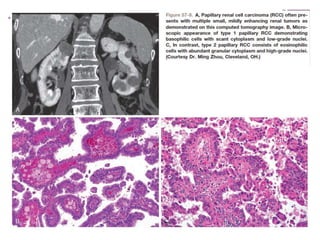

Papillary Renal Cell Carcinoma

 The 2nd most common histologic subtype .

 It represents 10% to 15%of all RCCs.